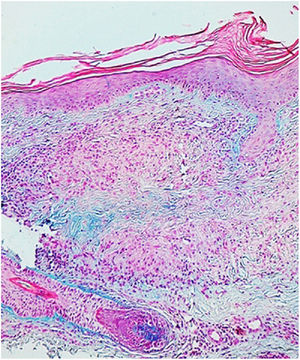

HistopathologyThe histopathology study showed a lymphohistiocytic infiltrate with palisading histiocytes surrounding a central area with necrobiosis and mucin deposit (Fig. 2).